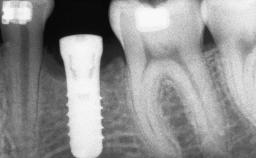

A 47-year-old Caucasian woman with a single-tooth edentulous space at the site of the left maxillary canine was referred for treatment. She had undergone traumatic extraction of this impacted canine several months before referral. Her chief complaint was the dissatisfying appearance of her smile. The patient desired a stable and esthetic rehabilitation of the site. Her dental history showed no evidence of periodontal disease or bruxism. She had no systemic diseases, was not taking any medications, and did not smoke. The extraoral examination revealed a high lip line and an inadequate soft-tissue volume at the defective canine site. Large black triangles were visible between the canine and its adjacent teeth.

Type of Implants Two-Piece

Bone Augmentation Staged|Vertical

Bone Volume Deficient vertically or deficient vertically AND horizontally